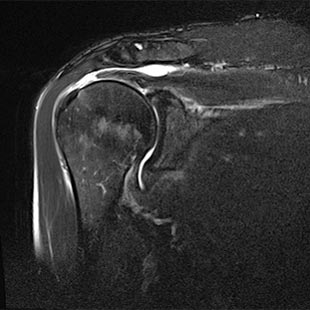

Rotatorenmanschettenruptur

(Sehnenabriss im Schultergelenk)

Abnutzungsbedingte Veränderungen im Alter und Stürze auf die Schulter oder auf die Seite können zu einem Riss der Rotatorenmanschette (= Muskel-Sehnen-Kappe der Schulter) im Schultergelenk führen. In den meisten Fällen ist die Supraspinatussehne betroffen.

Durch den Riss wird das subacromiale Engpaßsyndrom (Impingementsyndrom) verstärkt und eine Schleimbeutelentzündung unter dem Schulterdach unterhalten. Die Folge ist neben Ruhe- und Bewegungsschmerzen im Schultergelenk auch eine verminderte Kraft in der Schulter speziell für die Drehbewegung nach innen und außen, sowie bei der Armabspreizbewegung. Der abgespreizte Arm kann häufig nicht mehr gehalten werden und es findet sich eine deutliche Bewegungseinschränkung des betroffenen Schultergelenkes.